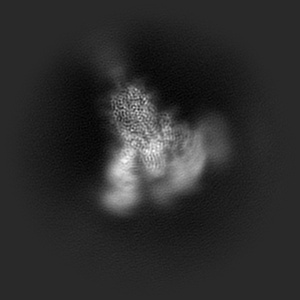

SARS-CoV-2 spike trimer (6P) in complex with three H18 and three R1-32 Fabs

Single-particle3.39 Å

Sample: SARS-CoV-2 spike trimer (6P) in complex with three H18 and three R1-32 Fabs